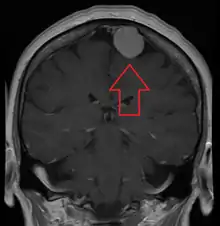

| A contrast-enhanced CT scan of the brain, demonstrating the appearance of a meningioma | |

Meningiomas are visualized readily with contrast CT, MRI with gadolinium,[22] and arteriography, all attributed to the fact that meningiomas are extra-axial and vascularized. CSF protein levels are usually found to be elevated when lumbar puncture is used to obtain spinal fluid. On T1-weighted contrast-enhanced MRI, they may show a typical dural tail sign absent in some rare forms of meningiomas.[17]